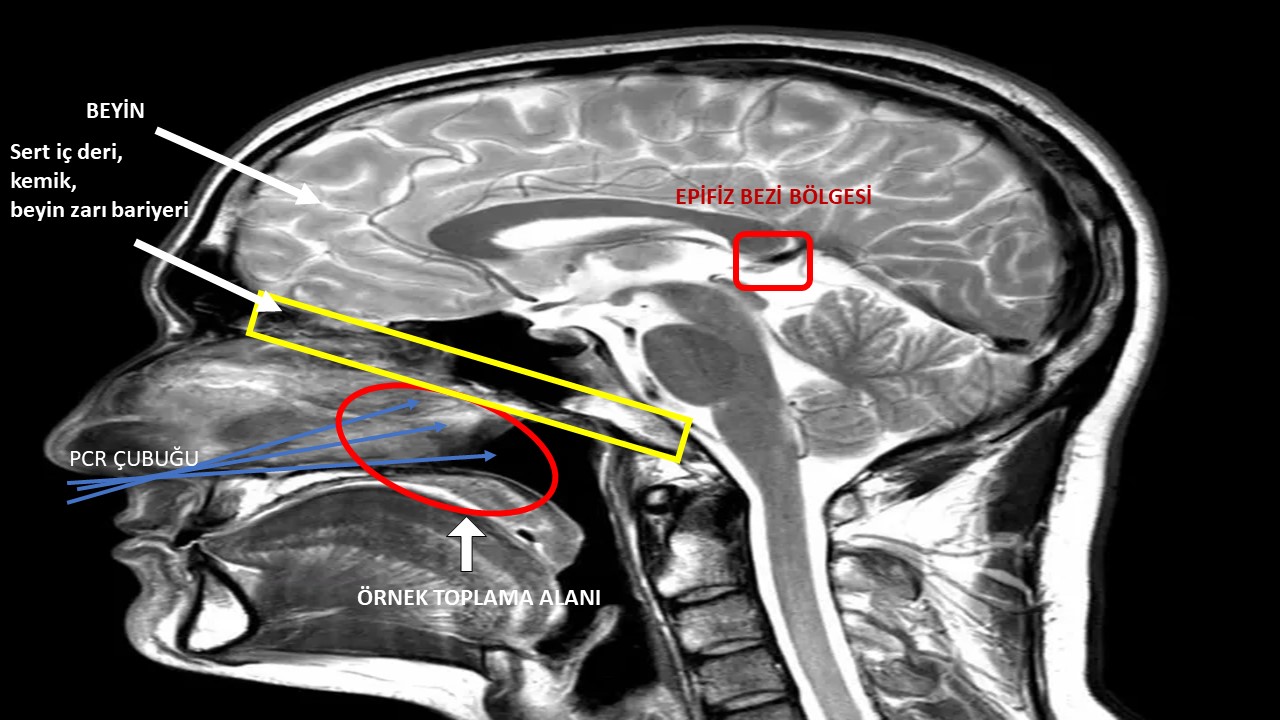

Görselde epifiz bezi (pineal gland) ve diğer birkaç beyin yapısı görülmektedir. Görüldüğü gibi epifiz bezinin yerleşimi oldukça uzaktadır; burun girişleri ile arasında çok uzak bir mesafe ve arada atlatılamayacak kadar çok sayıda yapı vardır. Sürüntü çubuğu, yutağa daha yakın olan hipofiz bezi (pituitary gland) gibi diğer yapılara kadar bile gitmemektedir, çok daha yukarıda ve uzakta olan epifiz bezine yetişmesi imkânsızdır.

Epifiz bezi, beynin orta/yukarılarında bir konumda iken, yutağın beyin ile bu bağlamda herhangi bir alakası bulunmamaktadır ve hiza olarak da beynin en alt kısımlarına denk gelmektedir.

Yukarıdaki görselde görüldüğü gibi yutak, beynin bir bölümü ya da uzantısı değildir. Sürüntü çubuğunun beyin ile kılcal damarlar arasında bulunan kan-beyin bariyerine herhangi bir şekilde ulaşması mümkün değildir. Burun dahil solunum yollarının hiçbir kısmı, beyne açılmamaktadır.